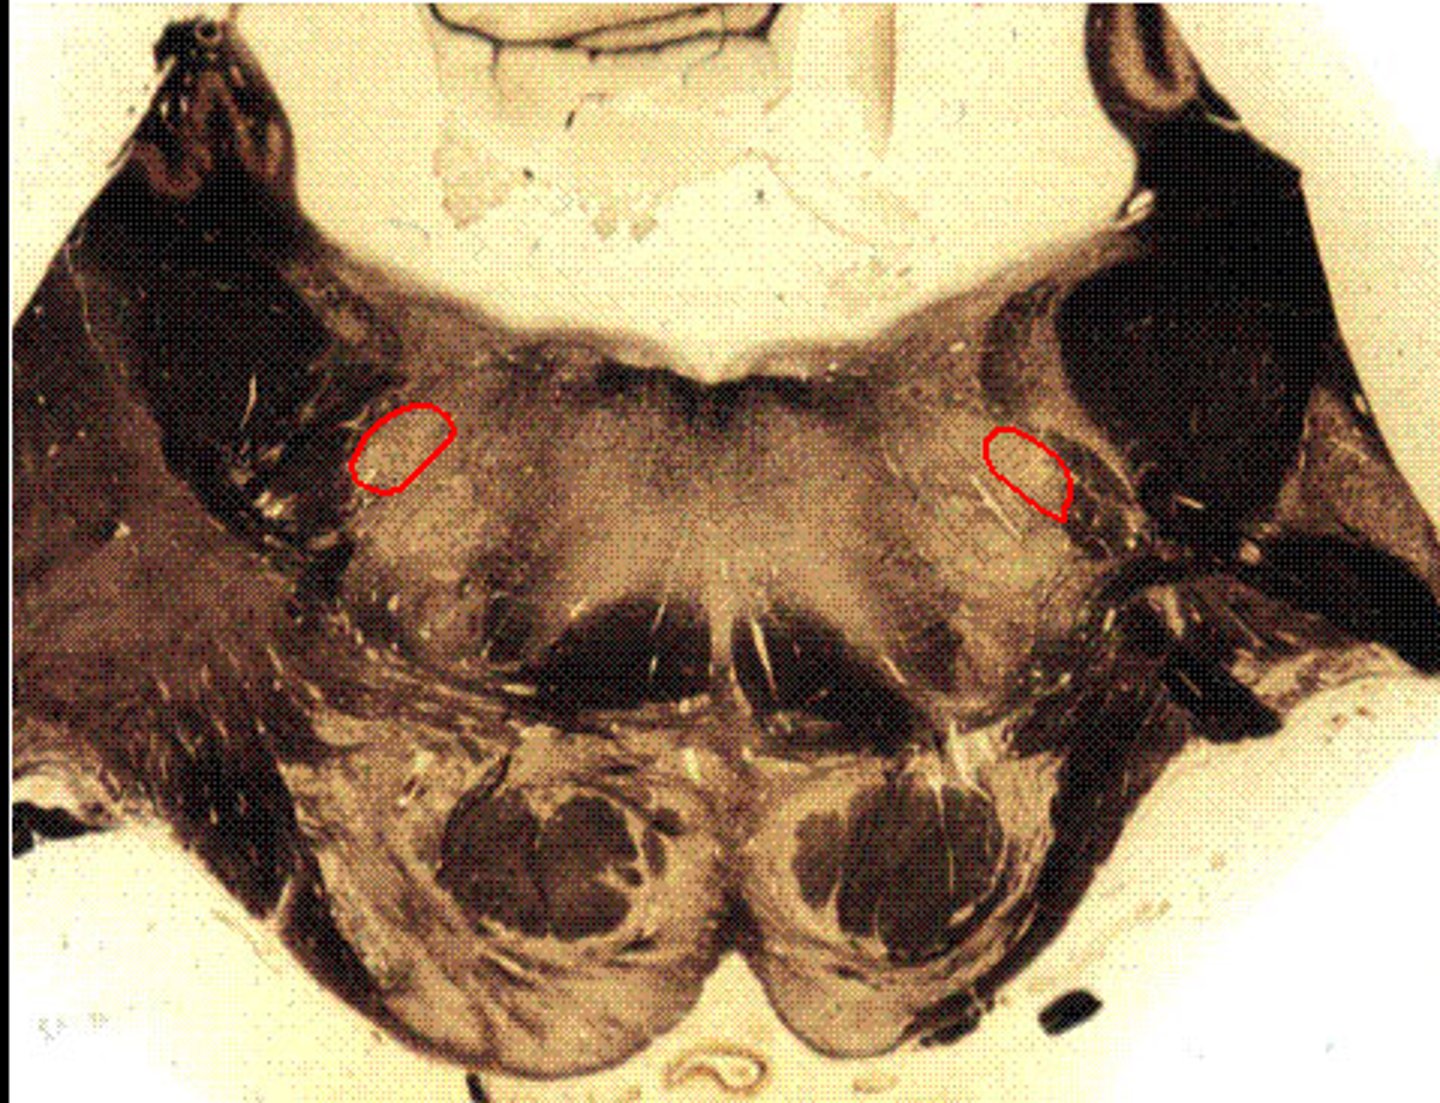

Rostrall Medulla

Inferior Cerebellar Peduncle

[aka "restiform body"]

Spinal Trigeminal Nucleus

Spinal Trigeminal Tract

Reticular Formation

Nucleus Ambiguous

Medial Lemniscus

Pyramid

Inferior Olivary Nucleus

Lateral Nucleus Cuneatus